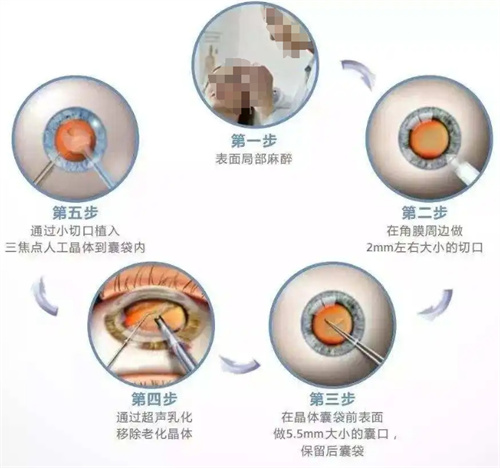

白内障手术是一种非常常见且安心的眼科手术,通常采用超声乳化技术将模糊的晶状体取出,然后植入人工晶状体以改善眼部视力。